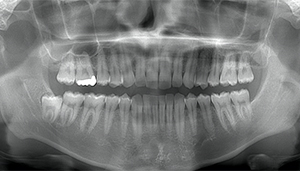

左下の歯茎が腫れている親知らずの症例

- 抜歯前写真(レントゲン、CT等)

左下の親知らず周囲歯肉が腫れていました。

また、手前の歯との間で虫歯もできていました。

| 抜歯内容 | 下顎の親知らずの抜歯希望の患者様です。 智歯周囲炎となっており、初診時では麻酔が効きづらい旨をお話しし、初診時は抗生物質をお出ししました。1週間後、ある程度歯肉の炎症がとれたことを確認して抜歯を行いました。 麻酔を行い、遠心(親知らずの奥側)歯肉と、手前の歯の頬側の歯肉を切開しました。 歯茎を開いて、手前の歯と引っかかっている部分をカットしました。 その後、骨からでている歯冠部(頭の部分)をカットしました。 その後へーベルで歯根(骨に埋まっている部分)を脱臼し、抜歯を終えました。 切開した歯茎を3針縫って、治療終了となりました。 歯茎を切ったため、3日ほど腫れぼったい感じがあったようですが、痛みはほとんどなく、治癒に向かいました。 |